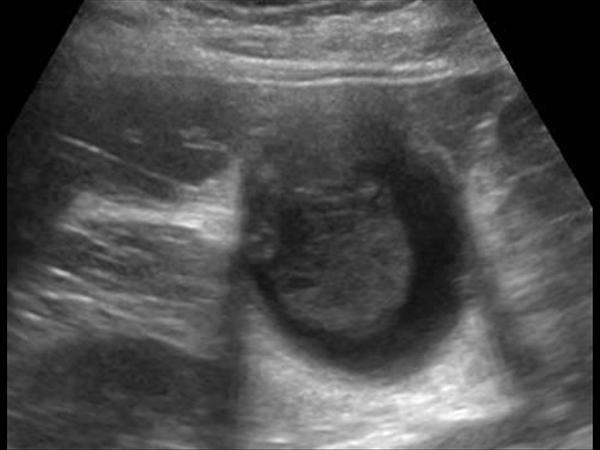

Bùn túi mật

» Thông tin: Nam giới – 40 tuổi.

» Lâm sàng: Đau mạn sườn phải.